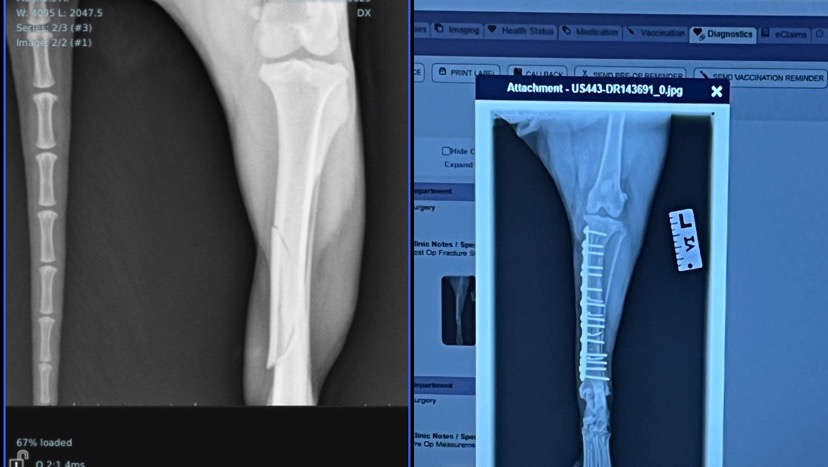

Kimchi is my little pug shepherd wonder pup and we became friends for life over 3 years ago. Earlier this week, Kimchi was attacked by a larger dog because he was chewing on a mint bone. The other dog pinned him to the ground and broke his left hind leg. We were fortunate enough to get Kimchi admitted to the animal hospital almost immediately, but unfortunately, the x-rays showed multiple fractures which would require surgical repair for him to be able to walk normally again.

Kimchi ended up needing to stay at the animal hospital the night before and after his surgery. During surgery, they inserted a metal plate with screws to hold the bone together. They also found additional bone splintering during the procedure, so they wrapped everything in wire to increase support for the bone to heal.